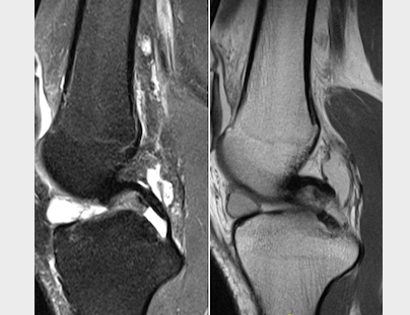

Total scapula replacement! One year follow up! Young teenage patient had an intraarticular resection...

Total scapula replacement! One year follow up! Young teenage patient had an intraarticular resection and free non vascularized fibula for an osteosarcoma in another country. The osteosarcoma recurred along the scapula and the fibula was eroding through the skin.